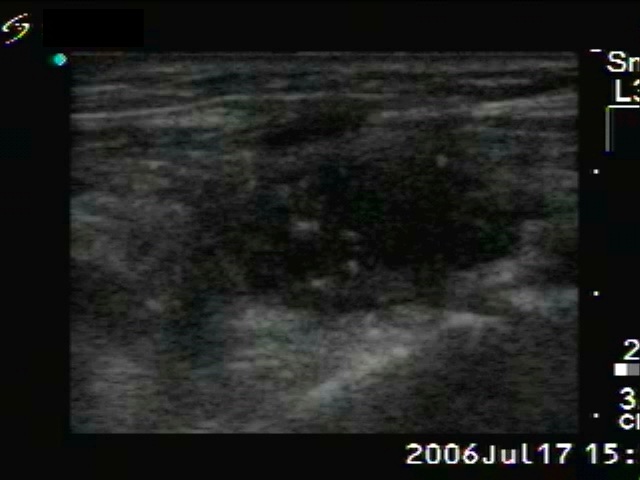

Medullary carcinoma (histological diagnosis)

The tumor has hyperechogenic granules and a larger echonormal irregularly shaped patch which corresponds to amyloid deposit. Note the dorsal acoustic shadowing.